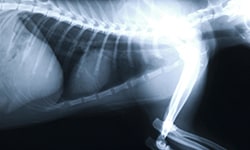

Eric Griesshaber provides animal wellness and emergency services for pet owners in the Silicon Valley.

Eric Griesshaber, D.V.M. / Veterinarian Cupertino CA